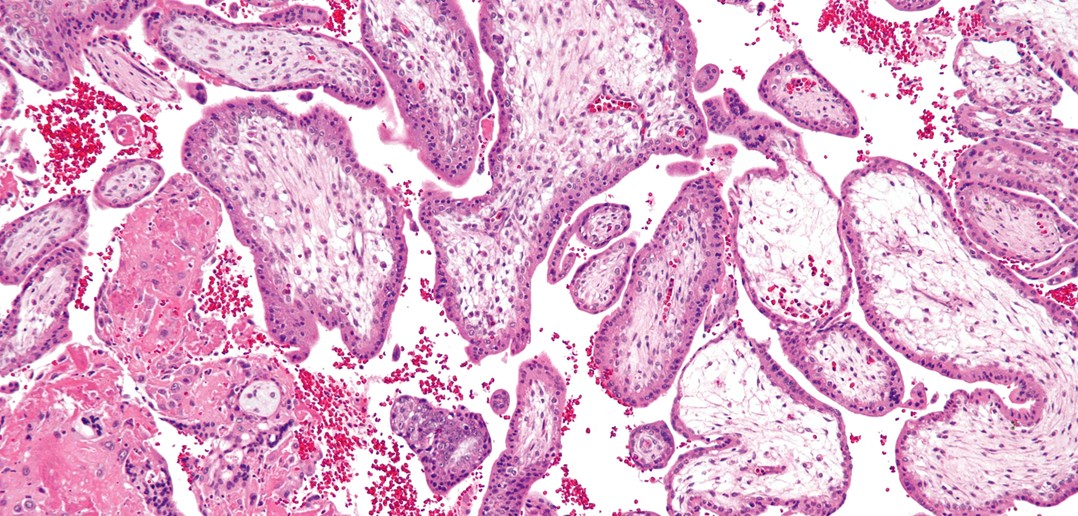

Lars Fändriks et Herbert Helander ont utilisé des techniques de microscopie quantitative pour déterminer la surface du tractus gastro-intestinal chez des adultes en bonne santé. Eux de nous apprendre que la surface fait seulement de 30 à 40 mètres carrés.

Le gros de la surface est occupé par le petit intestin, le gros intestin ayant une surface approximative de 2 mètres carrés, alors que la bouche, l’œsophage et l’estomac, tous confondus présentent une surface inférieure à 1 mètre carré, ce  qui est à peine la moitié d’un terrain de badminton.

Les deux chercheurs de la faculté de Göteborg ont utilisé des données fournies par investigations radiologiques, ainsi que de données obtenues par analyse microscopique du tractus gastro-intestinal, et ce afin d’obtenir des échantillons des membranes muqueuses des intestins.